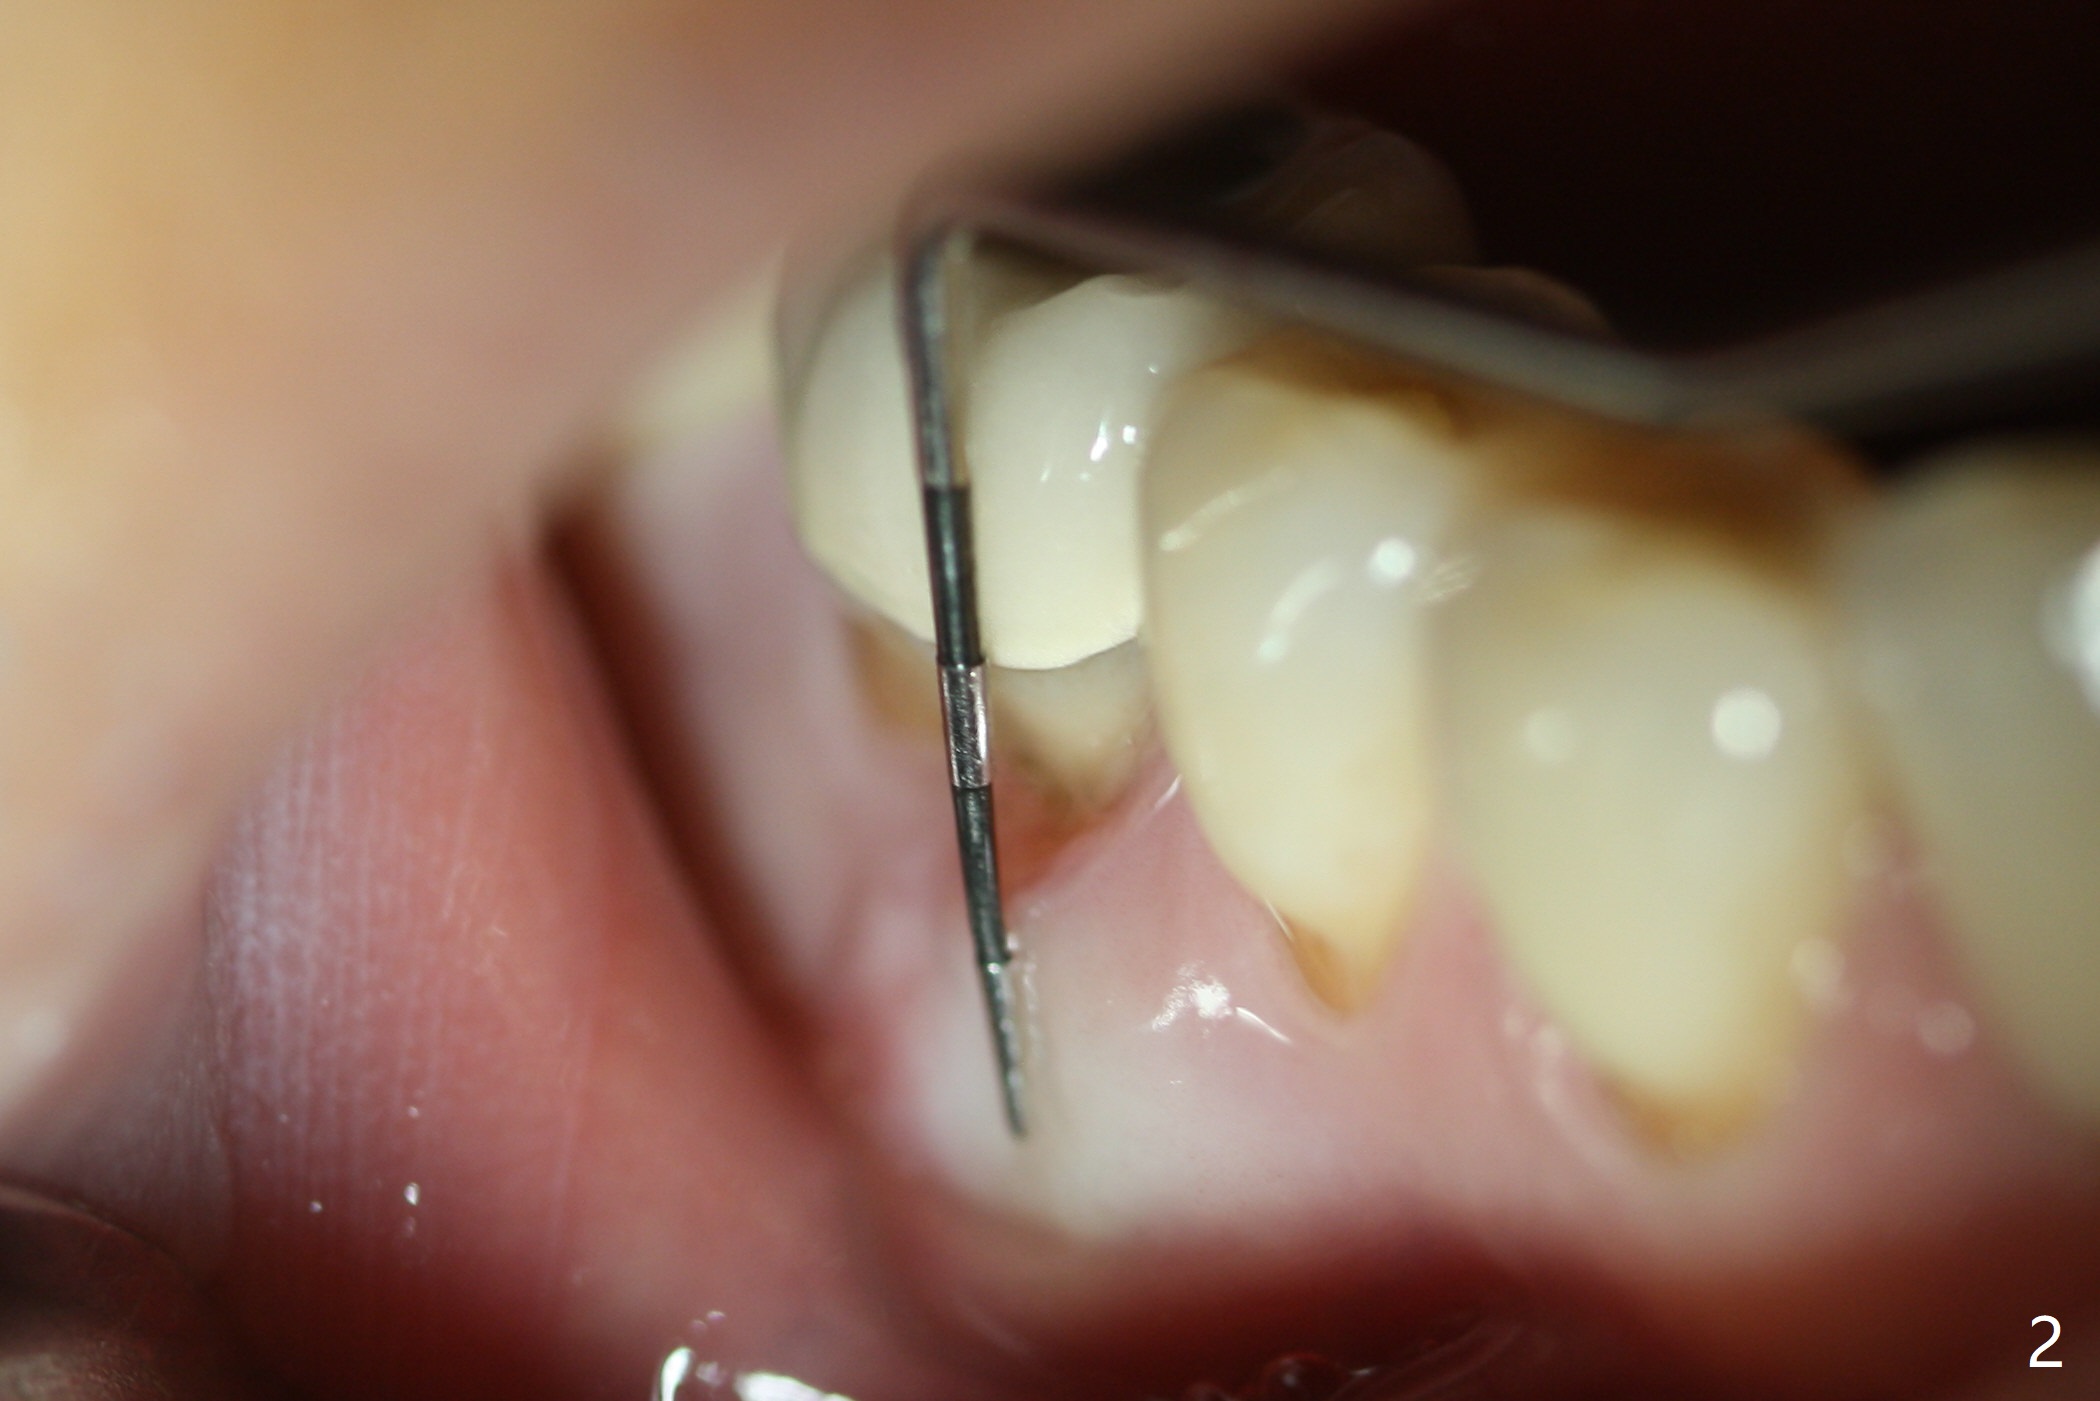

Preop oral Amoxicillin seems to be associated with reduction in the buccal and lingual (Fig.3 arrow) fistulae at #30, but there is mesiobuccal swelling (Fig.1 *) with 7 mm pocket (Fig.2). Osteotomy is initiated in the middle of the septum (Fig.3-5 S). As the osteotomy increases, it shifts mesially (Fig.6 arrow). Guided surgery is able to reduce shifting. A 5x13 mm implant is not seated completely (Fig.7) apparently due to osteotomy shifting. After removal of the bone from the osteotomy distally, the implant remains unseated with lower torque value (Fig.8). Following reuse of the 4.3 mm drill deeper by 1-2 mm, the implant is seated to a satisfactory depth (Fig.9 with increase in torque to 50 Ncm) with placement of Vera Graft (*) and a 7.5x4(3) mm abutment. After a second round of allograft placement (Fig.10 *), the implant is found to be 4 mm from the IAC. At the later stage of osteotomy, the coronal end of the septum is destroyed with loss of osteotomy depth landmark. It is apparent that the soft tissue landmark may be more reliable. The implant threads appear to be covered by the bone graft 3.5 months postop (Fig.11). The abutment is changed to 6.5x5(3) mm one before impression with minor margin prep. The bone density seems to increase 5 months postop, i.e., immediately post cementation (Fig.12) and 10 months postop (5 months post cementation (after retightening abutment), Fig.13 (*)). Periimplantitis develops mesiobuccally, consistent with bone loss 1 year 7 months post cementation (Fig.14 *); the implant seems to have been buccally placed. Bone graft is necessary with PRF or GEM21S if the vein is small and 6-month membrane with a hole around a 7.5x4(4) cemented abutment for easy wound closure. Take 5x5 CM CBCT to determine which wall has defect, buccal or lingual. Check mesial contact. If so, remove the crown, reseat the abutment (possible incomplete seating) and re-impress after bone graft.